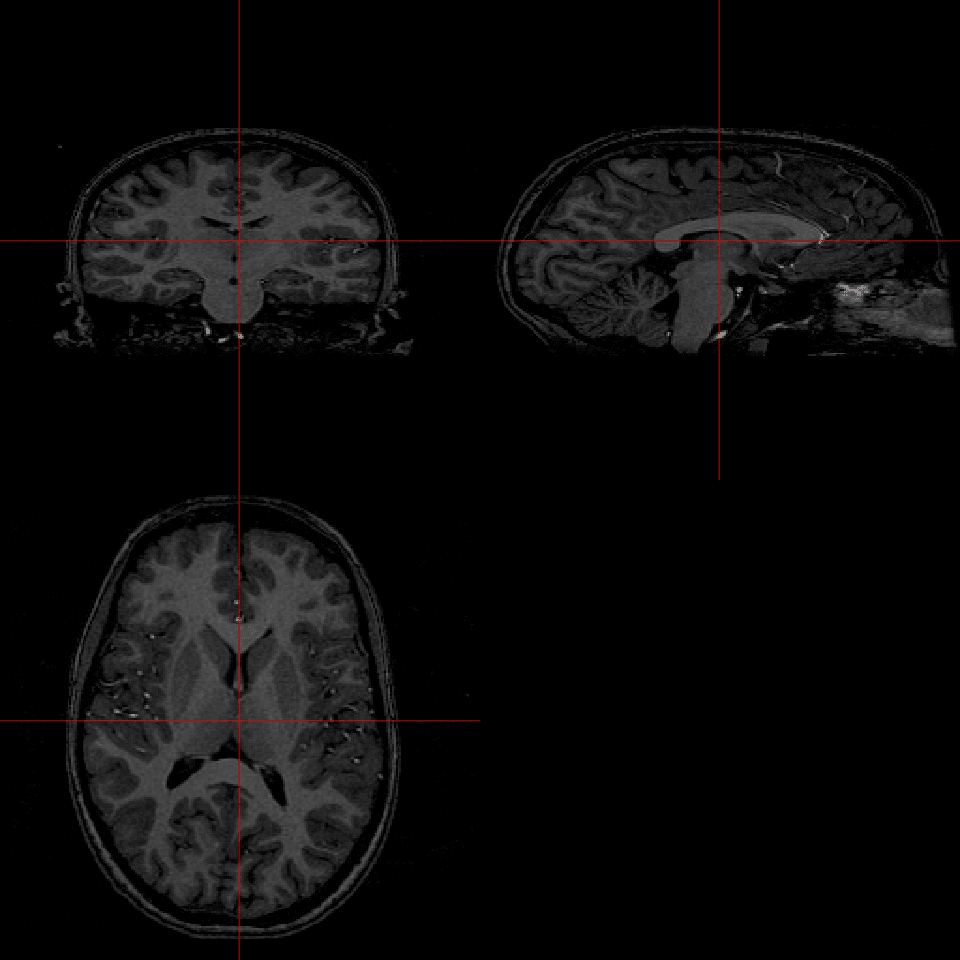

The first attempt at reading this file on line #2 fails. The error message is very informative, bytes 129-132 do not contain the characters DICM which is part of the DICOM Standard. So... it's safe to assume that this file is not a valid DICOM file. Delving further we turn on the debugging option (line #4) and are able to see what the first 128 bytes, which are skipped by default as part of the DICOM Standard, look like. They obviously contain information. By setting skipFirst128=FALSE and DICM=FALSE (line #13) we can override the default settings are start reading information from the first set of bytes. This does the trick and with the debugging option turned on every field from the header is displayed. No errors have occurred, so we can display the image data from this file (line #40) below.